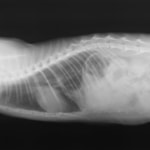

術前レントゲン

腹部臓器が胸腔内に脱出し、腹部と胸部の境界および心臓や肺の陰影が不明瞭になっています。また、胸腔内に消化管のガス陰影が認められます。